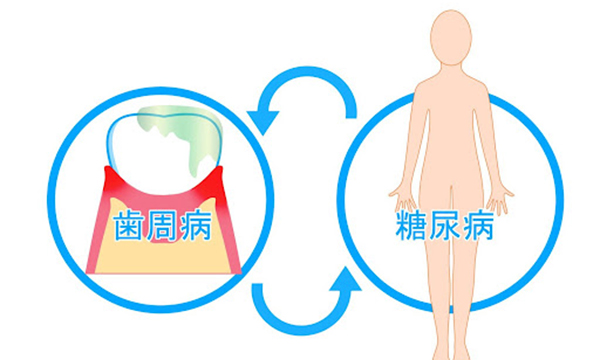

歯周病と全身疾患

歯ぐきの炎症によってできる炎症性物質(サイトカイン)は、血液を通して体内に入り、様々な病気を引き起こしたり、悪化させる原因となります。

糖尿病

炎症性物質が血糖値を下げるインスリンの働きを悪くさせます。

歯周病と全身疾患の関係

歯周病はお口の中の病気ですが様々な全身疾患との作用があり悪さを引き起こします。

歯周病と糖尿病

歯周病と糖尿病が関係しているというのを聞いたことがある人は多いかもしれません。糖尿病により高血糖状態が続くと歯周病菌が活性します。これにより歯周組織が壊され歯周病が進行していきます。

また、歯周病菌の毒素はインスリンの活性を悪くします。インスリンとは血糖値を保つために必要なホルモンですが歯周病により細菌が増えることで血糖値をうまく保つことが出来ず、糖尿病が悪化してしまいます。